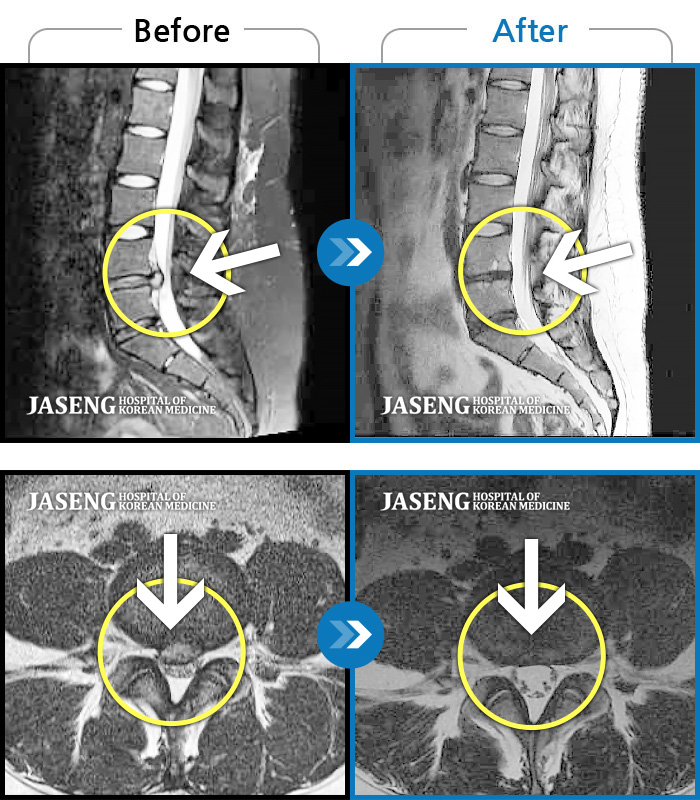

허리디스크

잠실 · 한상욱 원장

우측 엉치부터 우측 다리부터 발끝까지 저리고 아프다. 감각까지 먹먹하다.

촬영시기

2022.04.15 ~ 2022.10.22

2022.12.02